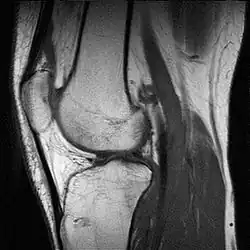

In addition, variants of false colors such as pseudocolors, density slicing, and choropleths are used for information visualization of either data gathered by a single grayscale channel or data not depicting parts of the electromagnetic spectrum (e.g. elevation in relief maps or tissue types in magnetic resonance imaging).

A pseudocolor image (sometimes styled pseudo-color or pseudo color) is derived from a grayscale image by mapping each intensity value to a color according to a table or function.[11] Pseudo color is typically used when a single channel of data is available (e.g. temperature, elevation, soil composition, tissue type, and so on), in contrast to false color which is commonly used to display three channels of data.[4]

Depending on the table or function used and the choice of data sources, pseudocoloring may increase the information contents of the original image, for example adding geographic information, combining information obtained from infrared or ultra-violet light, or other sources like MRI scans.[13]